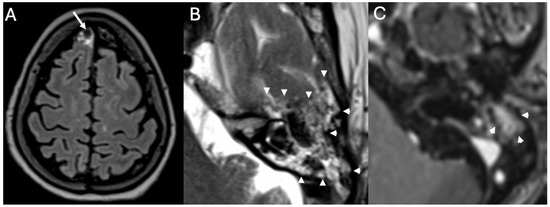

3.3. Cholesteatoma

3.3.1. Imaging

3.3.2. Complications

| Cholesteatoma and Otogenic Complications | Kuo et al., 2015 [26]; Baráth et al., 2011 [27]; Mustafa et al., 2014 [28]; Dubey et al., 2010 [29]; Sun et al., 2014 [30]; Lee et al., 2020 [31] | Reviews and retrospective studies | Cholesteatoma causes erosion and CSF leak, leading to meningitis (12–30% incidence); MRI improves detection; pediatric risk emphasized. |